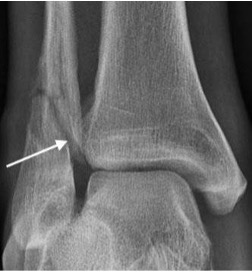

Talar neck fracture

- Impaction of talus on tibia during forced ankle dorsiflexion

- May lead to disrupted blood supply to the talar body with subsequent avascular necrosis

- The ‘Hawkin's sign' describes subchondral lucency of the talar dome 6-8 weeks after a talar neck fracture; indicates sufficient vascularity in the talus

- Absence of the Hawkins sign, seen as subchondral sclerosis may indicate disruption to the blood supply of the talar dome and underlying AVN

Hawkin’s sign with subchondral lucency of the talar dome (arrows)